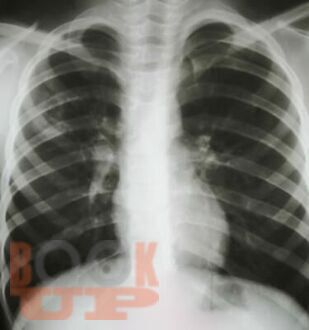

Учебное пособие составлено в соответствии с требованиями ФГОС ВО по специальностям 31.05.01 Лечебное дело и 31.05.02 Педиатрия, рабочей программы дисциплины «Фтизиатрия». В пособии представлена клиническая классификация туберкулеза, но сделан акцент на локализацию туберкулеза органов дыхания, иллюстрированная рентгенологическими снимками больных, лечившихся в КГБУЗ «Красноярском краевом противотуберкулезном

диспансере №1» с 1980-х г. по настоящее время, также даны определения различным формам туберкулеза органов дыхания.